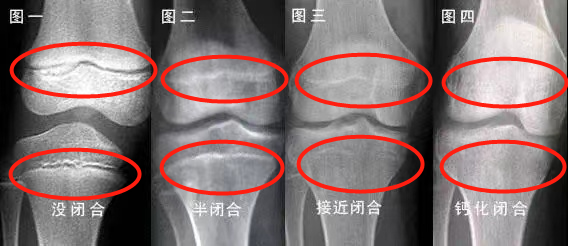

骨龄(BA)在很大程度上代表了儿童真正发育水平,能较准确地反映身高增长的空间,是判定矮小与否最重要的一个工具。正常来说,骨龄一般跟年龄相差一岁以内,都属于正常的范围。落后或超前过多即为异常。当骨骺线接近闭合时,基本上就没有什么长高的空间。

一般来说,男孩骨龄16岁闭合,女孩骨龄14岁闭合。如果孩子的骨龄偏大,就会比同龄人更早出现骨骺闭合,也就是说,剩余生长潜力减小。骨龄也不是越小越好,如果骨龄明显偏小,需要及时就诊儿科内分泌门诊,让专科医生进行评估!